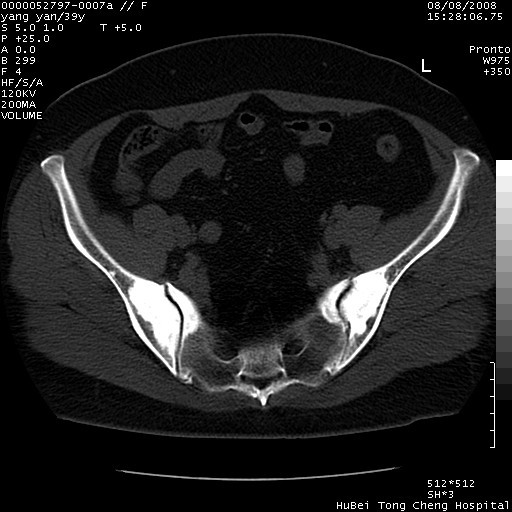

患者 女,39岁。因外伤检查,偶然发现。

典型!双侧骶髂关节致密性骨炎。

典型!病变主要累及双侧髂骨。常见于育龄期妇女。

致密性骨炎,一般不跨越关节面,可是这个骶骨关节面也有硬化。

髂骨致密性骨炎系一种以骨质硬化为特点的非特异性炎症,有高度致密的骨硬化现象,尤其以髂骨下2/3更为明显,但关节间隙则无改变。因位于骶髂关节,且该关节症状明显,故又称之为“骶髂关节致密性骨炎”。 本病90%以上为中年女性,以妊娠后期、尤其分娩后为多见,亦可见于尿路或女性附件慢性感染后,或盆腔内其他感染。此外,臀骶部的外伤亦可诱发或引起本病。  妊娠、分娩及外伤均可引起骶髂关节韧带的撕裂而易使局部的血供受阻。因此早期局部呈现充血、水肿及渗出增加等,渐而局部出现增生与变性反应,随着胶原纤维的致密化而向硬化演变;血管形成厚壁血管,易闭塞而引起髂骨耳状面处缺血和缺氧,骨质呈现硬化性改变,以致手术时局部出血较少。骶髂关节囊壁显示纤维增生、弹性降低及松动样改变。继发于盆腔内炎症者亦出现相类似的病理改变,可能系细菌内毒素作用所致。